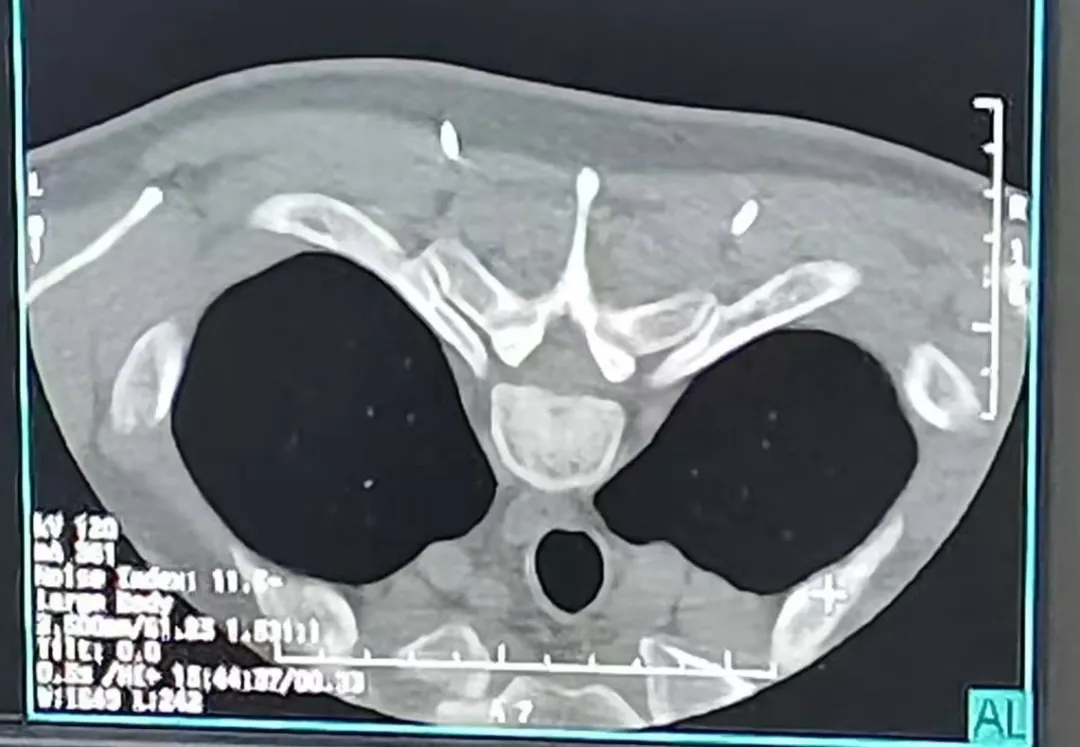

患者,男,45岁,诊断为“多汗症”,严重影响日常生活,行CT引导下双侧胸交感神经毁损术,患者术后双手及双足多汗症状明显缓解。